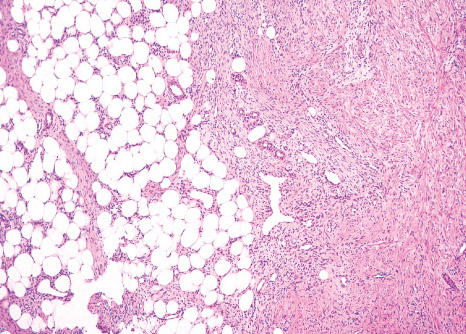

Histopathology:

characterized by three distinct components forming organoid

structures.

The well defined intersecting trabeculae of dense

fibrocollagenous tissue are composed of fibroblastic and

myofibroblastic spindle cells with bland, straight or wavy

nuclei separated by varying amounts of collagen.

Between fibrous trabeculae are islands of immature-appearing

small, rounded or stellate, primitive mesenchymal cells with

scant cytoplasm embedded in myxoid matrix containing

abundant hyaluronidase-sensitive acid mucopolysaccharides.

The primitive myxoid areas are frequently oriented around

small veins.

The mature fat component is interspersed among the other

two components.

The relative proportions of these components vary between

cases.